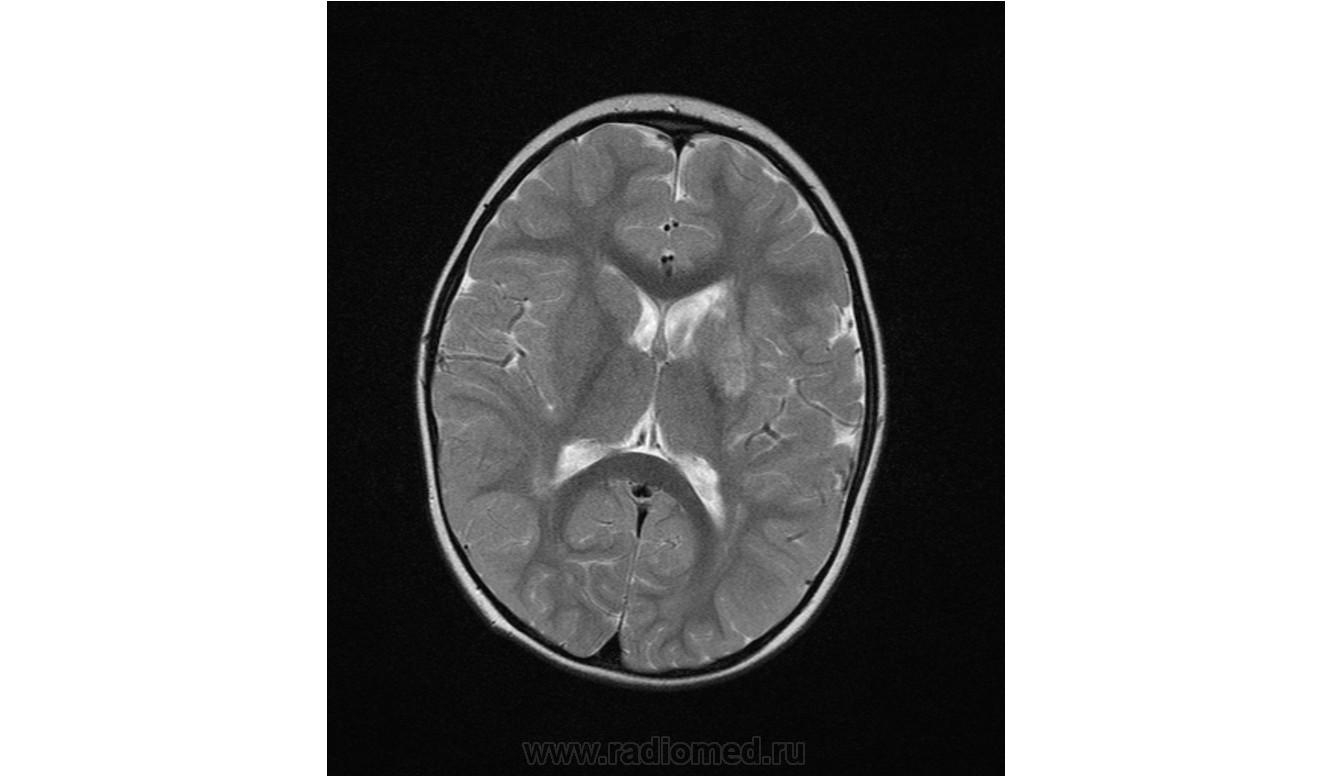

Ребенок 2 года, заболели в середине декабре, гемипорез, к сожелению не могу ни как с контрасном исследованеим здесь загрузить но накапление контрасного вещества нет, спосибо за помочь!!!!!!!

Предположу гипоксически-ишемические изменения с диапедезным кровоизлиянием. Но они чаще двусторонние.